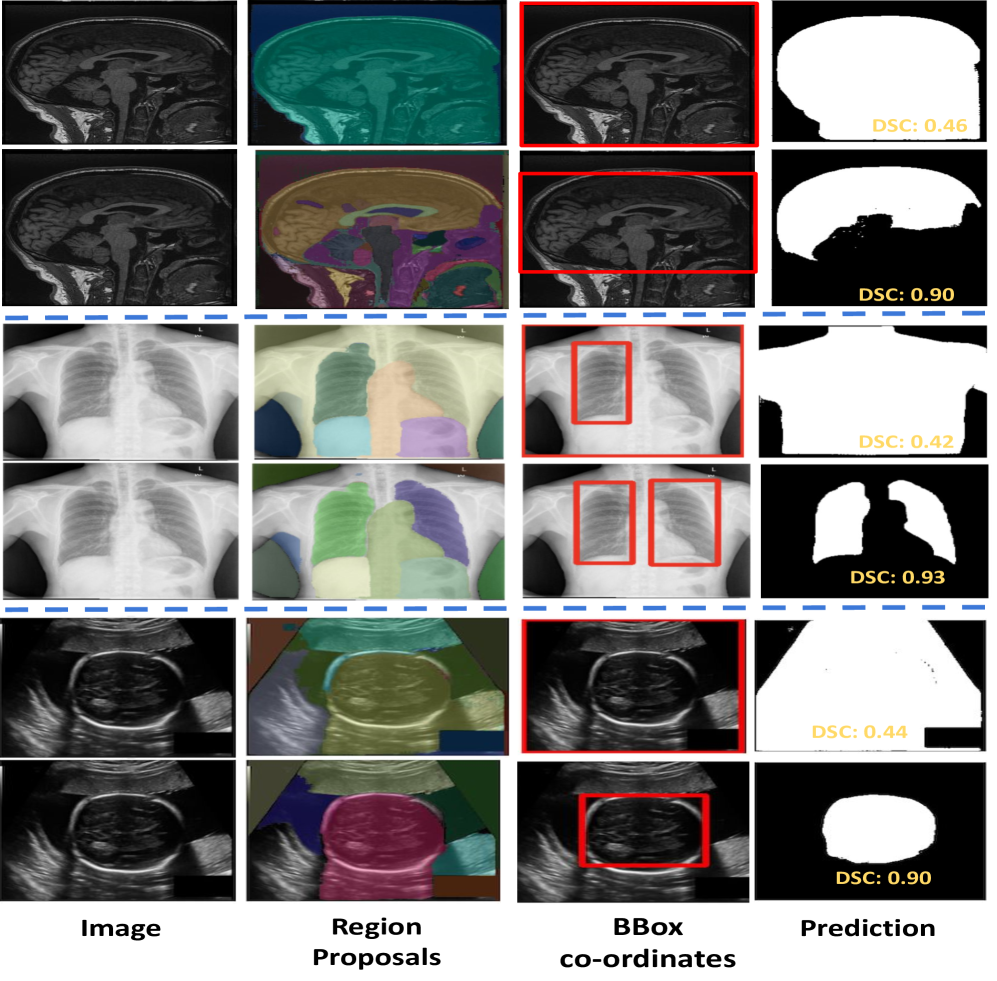

Refer to caption

Figure 6: Ablation: the first row for each modality shows results without area filtering, and the second row illustrates the effects of area filtering (ours).

4.4.3 Area based filtering

𝑆𝐴𝑀𝑬𝑴subscript𝑆𝐴𝑀𝑬𝑴\mathbf{\textit{SAM}}_{\textbf{{EM}}}SAM start_POSTSUBSCRIPT EM end_POSTSUBSCRIPT employs a grid-wise set of key points to generate masks for each part of the image. The resulting set of masks may include masks for the background or larger regions encompassing the region of interest (ROI). In such cases, CLIP can miss-classify background or larger region encompassing ROI as ROI as illustrated in  Fig. 6. To tackle this challenge, we implement area-based filtering, determining the optimal area threshold through a random hyperparameter search. To assess the effectiveness of this filtering approach, we compare its results with those obtained by passing all the masks generated by 𝑆𝐴𝑀𝑬𝑴subscript𝑆𝐴𝑀𝑬𝑴\mathbf{\textit{SAM}}_{\textbf{{EM}}}SAM start_POSTSUBSCRIPT EM end_POSTSUBSCRIPT to CLIP without any filtering. The comparative results between area filtering and without area filtering are presented in  Tab. 6. Our area filtering approach shows an improvement of 3% for brain segmentation [25] and approximately 10% for lung and fetal head segmentation [19].